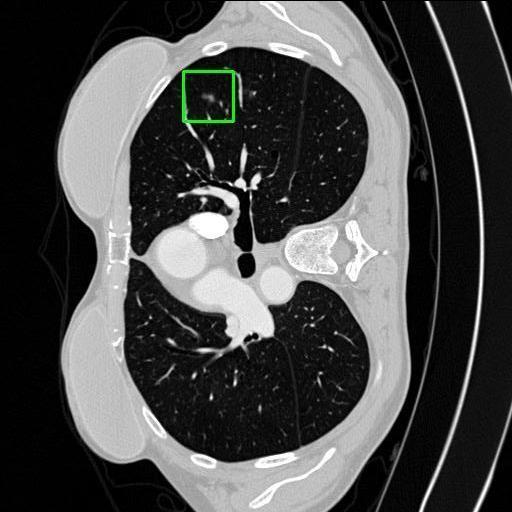

We developed an AI-based system using deep learning models for analyzing lung CT scans to detect and classify pulmonary nodules. We chose the YOLOv11 architecture for its enhanced object detection capability and adapted it specifically for medical imaging, incorporating pixel-level precision and severity classification.

Classification into three severity levels with colored bounding boxes.

Successfully built and deployed an AI model (YOLOv11) capable of detecting lung nodules in CT scans with high accuracy and real-time performance.

Designed a severity classification system that categorizes nodules into null, moderate, and severe using colored bounding boxes, assisting in rapid clinical decision-making.